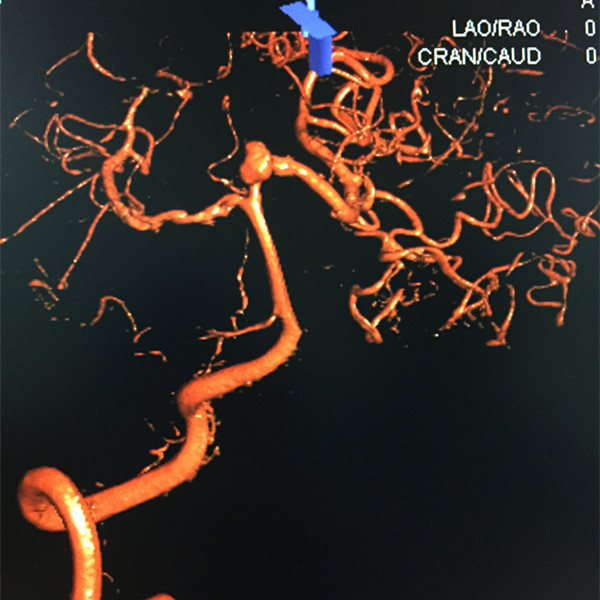

术前3D造影

动脉瘤大小

本例患者张某,老年女性,主因发现烟雾病2月余,为行脑血管造影术进一步明确诊断而入院,入院后全脑DSA发现双侧颈内动脉末端闭塞,符合烟雾病的诊断,令人担忧的是,在造影的同时发现患者左侧大脑后动脉P1段动脉瘤,大小4.25*6.40mm,形态不规则,目前对于未破裂动脉瘤的治疗要综合考虑病人的年龄、身体状况、有无其他致命疾病以及病变部位等等,评估患者是否能获益。就该患者而言,其脑内供血动脉由双侧椎基底动脉及颈外动脉代偿向颅内供血,一旦大脑后动脉动脉瘤破裂后果不堪设想,经过神经外科王劲教授、王贵怀教授、苏伟主治医师及范玉龙医师商讨后,对于合并烟雾病的颅内动脉瘤患者,特别是动脉瘤部位位于基底动脉分叉以后的大脑后动脉近侧端,手术风险极大,不适合开刀手术治疗,建议神经介入栓塞治疗。在国内知名神经外科介入专家北京天坛医院杨新健教授指导下,我院神经介入团队于2015年6月23日行支架辅助弹簧圈动脉瘤栓塞治疗。尽管介入操作创伤较小,但由于患者合并烟雾病导致双侧大脑中动脉闭塞,从而加大了手术难度和风险。不管是动脉瘤破裂还是载瘤动脉(基底动脉或大脑后动脉)闭塞,患者都将必死无疑。在顶住巨大压力后,在全麻下施行术中3D脑血管成像后,经过周密测量和反复讨论,由于动脉瘤瘤颈宽,需要使用Solitaire支架辅助弹簧圈栓塞治疗。经过近4个小时的治疗,动脉瘤成功被栓塞,患者安返ICU监护并于第二天返回普通病房,术后无新发不适,术后第四天病人即出院,最终将这颗“不定时炸弹”安全解除。